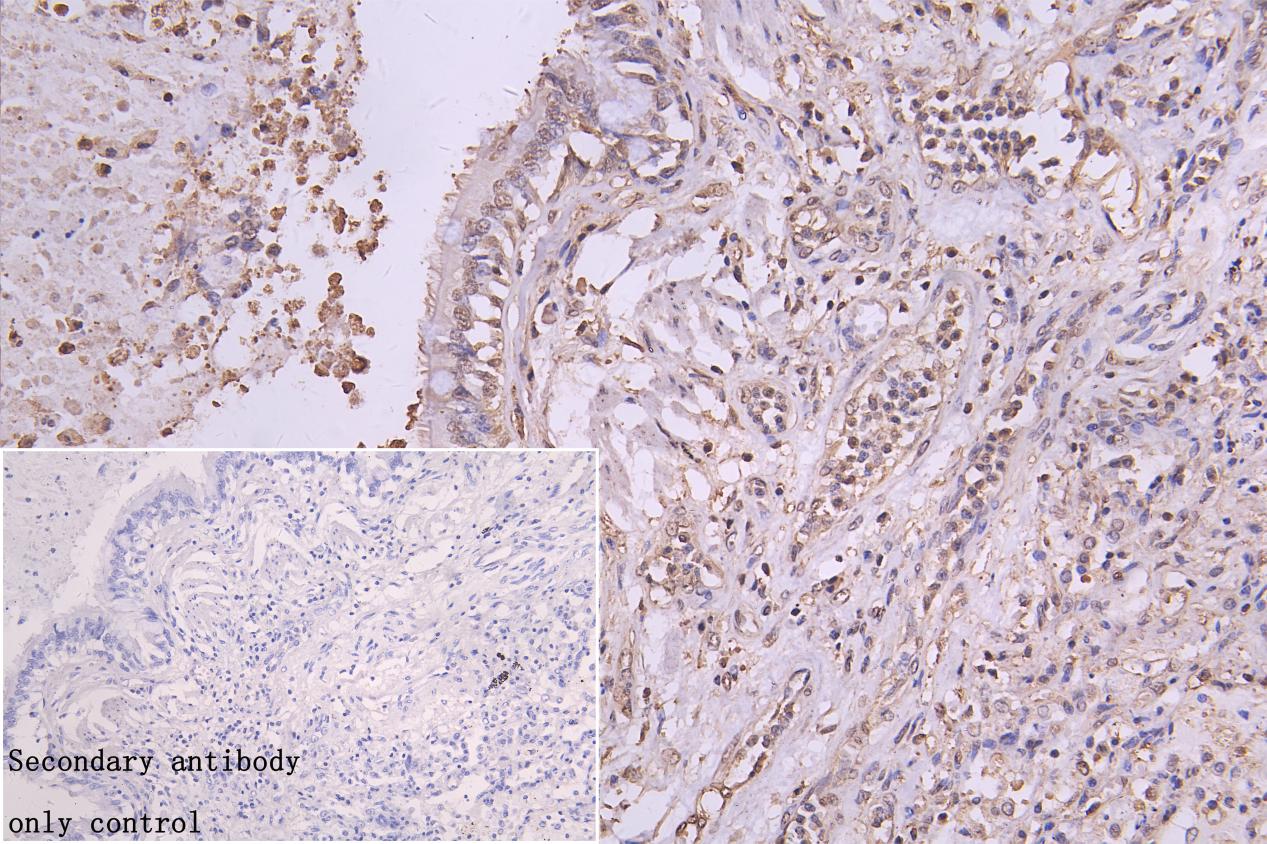

IHC image of CSB-RA616077A0HU diluted at 1:50 and staining in paraffin-embedded human lung cancer performed on a Leica BondTM system. After dewaxing and hydration, antigen retrieval was mediated by high pressure in a citrate buffer (pH 6.0). Section was blocked with 10% normal goat serum 30min at RT. Then primary antibody (1% BSA) was incubated at 4°C overnight. The primary is detected by a Goat anti-rabbit polymer IgG labeled by HRP and visualized using 0.05% DAB. Secondary antibody only control: uses 1% BSA instead of primary antibody